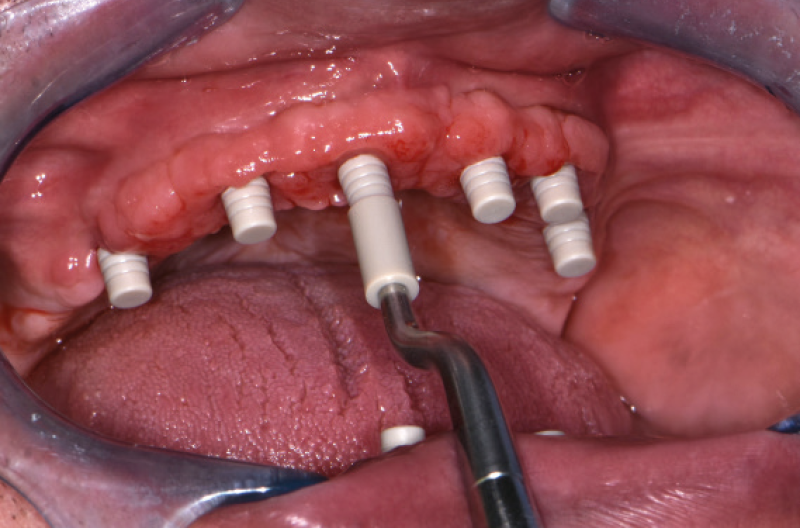

Dopo 4 mesi ho rivisto il paziente per la realizzazione della Toronto conometrica provvisoria nellŌĆÖarcata superiore (Figg. 26-29).

Fig. 26 – OPT a 4 mesi dallŌĆÖintervento

Fig. 27 – Situazione clinica a 4 mesi dallŌĆÖintervento

Fig. 28 – Vista dei monconi MUA-Conic nellŌĆÖinferiore a guarigione avvenuta

Fig. 29 – Guarigione del superiore